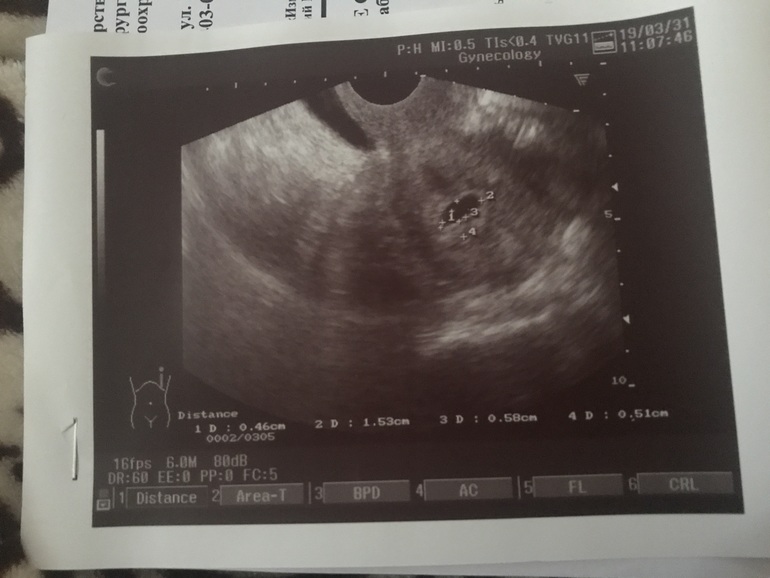

И мне написали плодное яйцо 15 на 6 мм, это какой диаметр?

(15+6):2=11мм это примерно 5 акушерских недель. Сужу по своей последней беременности, где 14 мм было в 5+5 недель с О на 13дц. А тонус вам не ставили?